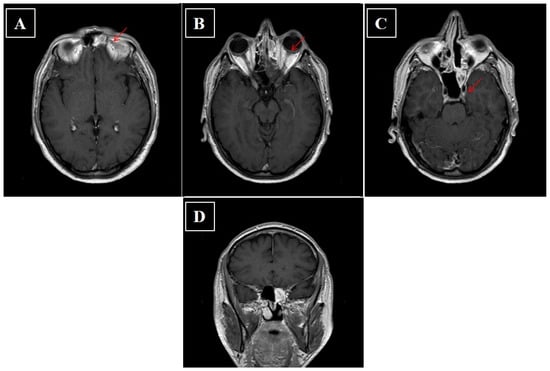

4.9. Olfactory Neuroblastoma (ONB)

- Jayme, E.M.; Morimoto, T.P.; Lozano, T.M.; Campos, Z.M.D.S.; De Castro, C.C. Sphenoid sinus neuroendocrine carcinoma. BJR Case Rep. 2017, 3, 20150334. [Google Scholar] [CrossRef] [PubMed]

- Westerveld, G.J.; Van Diest, P.J.; Van Nieuwkerk, E.B. Neuroendocrine carcinoma of the sphenoid sinus: A case report. Rhinol. J. 2001, 39, 52–54. [Google Scholar]

- Flavahan, P.W.; Keir, J.; Srinivasan, V. Neuroendocrine carcinoma of the ethmoid sinuses treated with radiotherapy alone. J. Laryngol. Otol. 2012, 126, 1066–1068. [Google Scholar] [CrossRef]